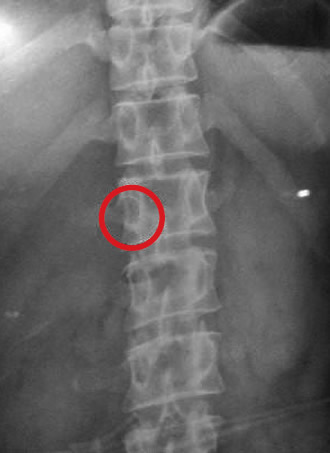

后经CT腹部侧位片显示,断针位于王女士体内脊柱骨前方约2厘米的位置,长约8mm(如图内圈处)。